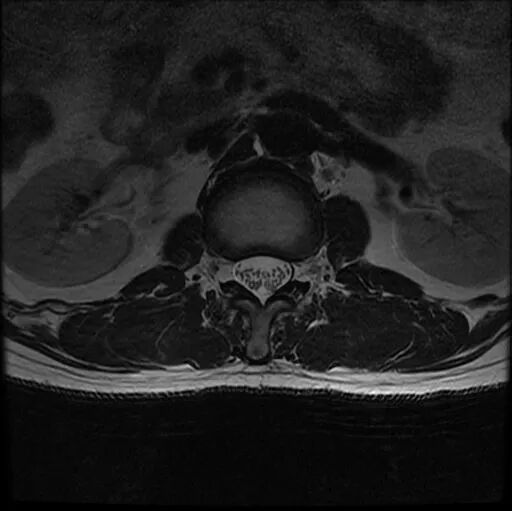

圖2:術(shù)前MRI

術(shù)前影像資料